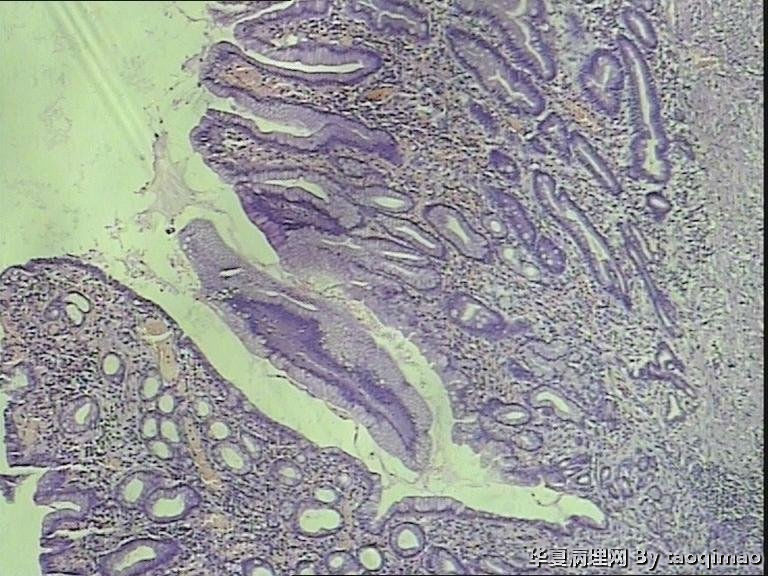

胃溃疡?

• 胃溃疡?图1

补取的组织

79岁女,胃溃疡,切除胃大部分,与脾有粘连,胃小弯侧可见一溃疡3x2.5x2cm,并且局部胃粘膜增厚,呈皮革胃样外观,切面灰白似粘液样。

胃低分化腺癌

令人困惑的切片!

肉眼既是巨大溃疡又是皮革胃,建议最好再取材,因为牵涉到后期治疗问题。

胃溃疡,黏液变,没看到明确的上皮样细胞

巨大溃疡临床诊断,可是看了间质很浆糊,希望老师们给指点些